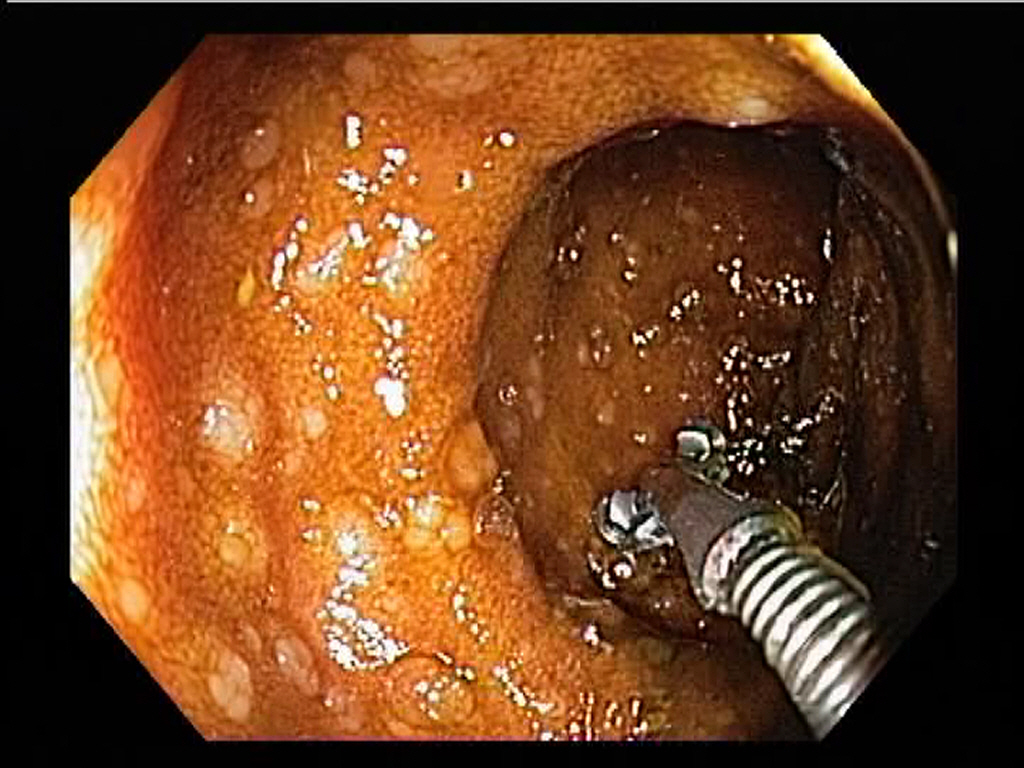

Terminal Ileum: Lymphoid Hyperplasia